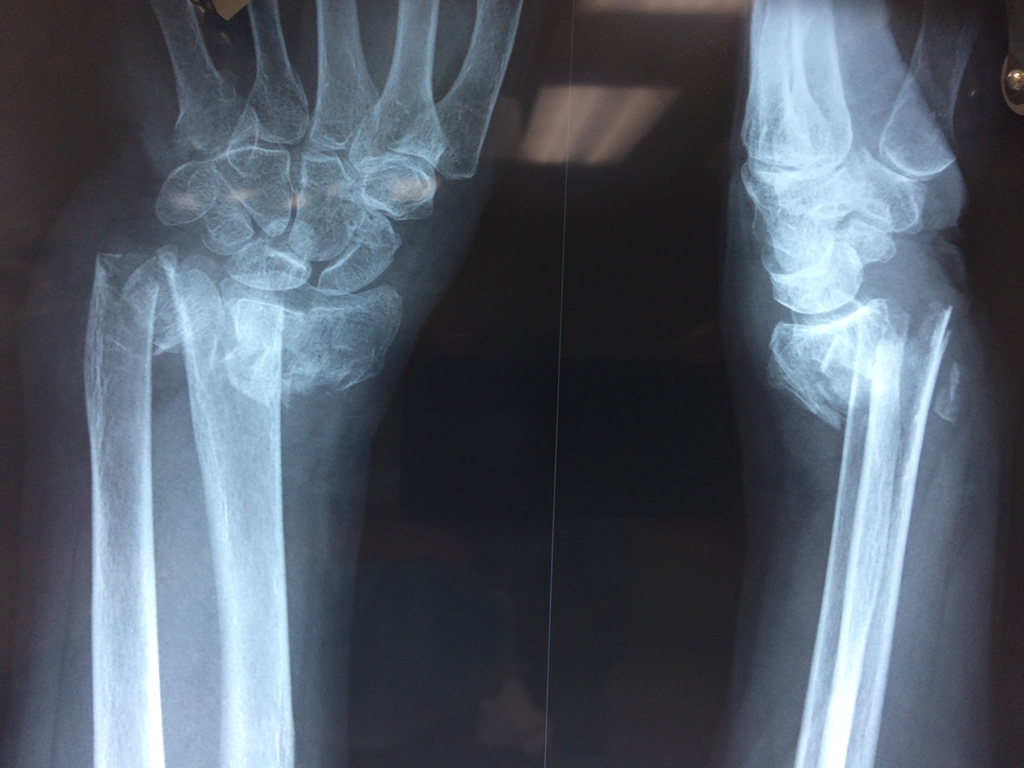

Cirugías de Húmero - Cirugías de Muñecas y Manos

Los procedimientos más comunes en cirugía de la mano son aquellos destinados a reparar traumatismos, incluyendo lesiones de tendones, nervios, vasos sanguíneos, y articulaciones; huesos fracturados; y quemaduras, cortes, y otros daños de la piel.